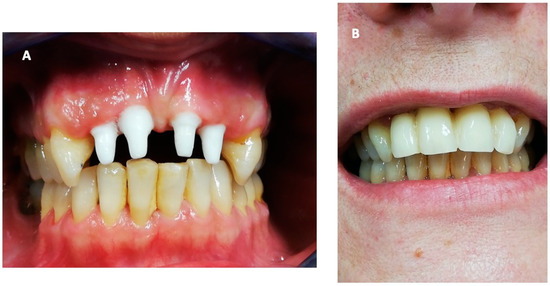

Hyperbaric Oxygen Therapy and A-PRF Pre-Treated Implants in Severe Periodontitis: A Case Report

2. Case Report